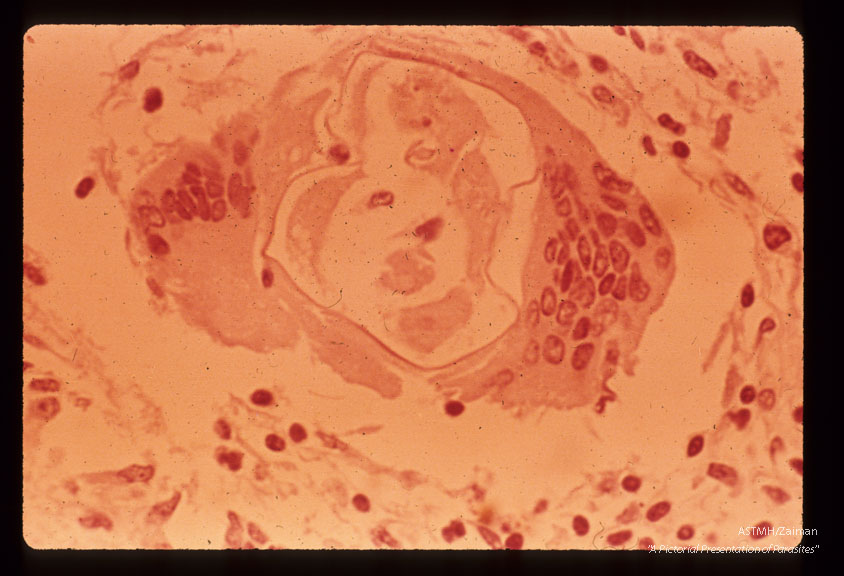

Cross section of nematode in monkey cord showing giant cell formation around worm.

Angiostrongylus cantonensis

Description: Cross section of nematode in monkey cord showing giant cell formation around worm.